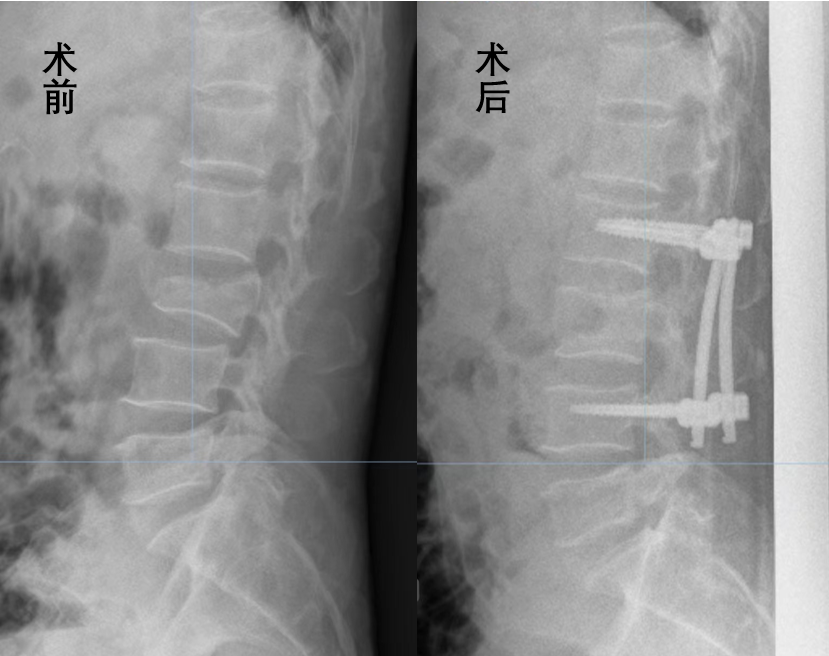

近日,茂名市人民医院脊柱外科一区专家团队成功利用天玑骨科手术机器人为68岁的从3米高处摔下、导致L3压缩骨折的蓝伯完成手术。术后,蓝伯恢复情况良好,很快达到出院标准,出院回家休养了。

考虑到蓝伯年龄较大,为降低日后出现椎管狭窄症状风险的同时取得更好的手术预后,专家团队制定了腰椎骨折切开复位钉棒系统内固定术的微创手术方案,并确定了在天玑骨科机器人导航下辅助手术的模式,获得了病人及家属的充分理解和支持。

在做好充分准备后,手术如期进行。专家团队熟练、灵活地运用天玑骨科机器人,精准定位骨折部位,通过微小的切口完成了该部位复原及固定,手术过程顺利、成功,一个小时便完成了。